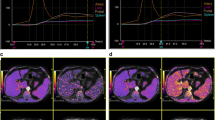

Portal vein pressure (r = 0.72, p < 0.001) and direct HVPG (r = 0.50, p = 0.003) were significantly correlated with splenic ECV in cirrhotic patients (see Fig. 1). A correlation matrix is given in Table 2.

Splenic ECV revealed a perfect diagnostic performance with an area under the curve (AUC) of 1.000, a sensitivity of 100%, and a specificity of 100% (see Fig. 2, Fig. 3, and Table 4). There were no significant differences in the diagnostic performance of splenic and hepatic ECV (AUC, 1.000 vs. 0.954; p = 0.116). The diagnostic performance of splenic ECV was also not significantly higher compared with that of hepatic native T1 (AUC, 1.000 vs. 0.926; p = 0.105) but significantly higher than that of splenic native T1 (AUC, 1.000 vs. 0.806; p = 0.005). There were no significant differences in the diagnostic performance of native splenic and hepatic T1 (AUC, 0.806 vs. 0.926, p = 0.058). Hepatic ECV showed a higher diagnostic performance compared with native splenic T1 (AUC, 0.954 vs. 0.806, p = 0.038). Between hepatic ECV and hepatic native T1, no significant differences in diagnostic performance were observed. The diagnostic performance of hepatic and splenic T2 was significantly lower than that of the splenic and hepatic native T1 and ECV parameters.

Graphs show receiver operating characteristic curves for diagnosis of clinically significant portal hypertension (direct hepatic venous pressure gradient, ≥ 10 mmHg) in the derivation cohort. Curves are given for hepatic T1 relaxation times (area under curve [AUC], 0.926), hepatic ECV (AUC, 0.954), hepatic T2 relaxation times (AUC, 0.731), splenic T1 relaxation times (AUC, 0.806), splenic T2 relaxation times (AUC, 0.736), and splenic ECV (AUC, 1.000)

Portal hypertension initially develops because of increased intrahepatic resistance to the passage of blood flow through the liver as a consequence of hepatic fibrotic changes. In this regard, splenomegaly in liver disease is likely to be a consequence of portal congestion with blood pooling as well as pulp hyperplasia and fibrosis [26]. All these changes lead to an expansion of the extracellular space, which is reflected in increased splenic ECV, as shown in our data. In our study, splenic ECV values were also significantly correlated with portal pressure and with direct HVPG.

To our knowledge, there are still no studies directly showing correlations between invasive measured direct HVPG in patients with end-stage liver disease and clinically significant portal hypertension and splenic ECV as a non-invasive marker of portal pressure. Splenic ECV showed a perfect diagnostic performance for clinically significant portal hypertension with an AUC of 1.000 in the derivation cohort. Moreover, although not statistically significant, the diagnostic performance of splenic ECV was superior to that of the liver, possibly because liver fibrosis reflects only one element of pathophysiological changes in portal hypertension, while splenic ECV directly reflects all consequences of portal hypertension (congestion, tissue hyperplasia, and fibrosis). ECV measurements also showed a higher diagnostic performance compared with T1 and T2 mapping parameters, probably because ECV is a physiologically normalized measure and reflects changes of splenic parenchyma more accurately. Therefore, ECV seems to be a stable and biologically significant biomarker for non-invasive assessment of portal hypertension.